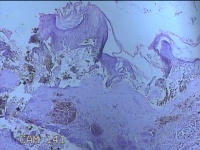

面部、下颌肿物

性别

女

年龄

36岁

临床诊断

皮脂腺囊肿

一般病史

无

标本名称

大体所见

灰白暗红色带皮肤样肿物1.3x0.8x0.3cm一个,表面光滑,起开肿物呈实性,切面灰白暗红色,质软。